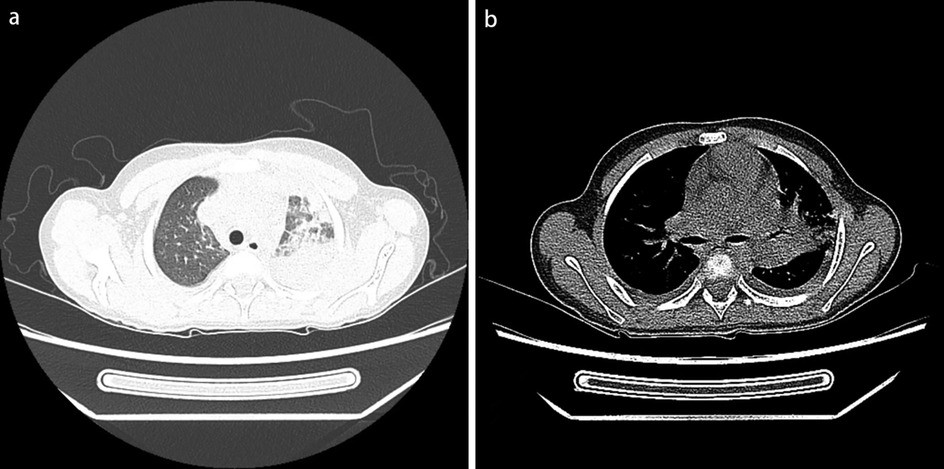

Physical examination upon admission: Temperature 38.4°C, no obvious conjunctival congestion, no dryness or redness of the lips, no “strawberry tongue,” no changes in extremities, several enlarged lymph nodes palpable in the neck. Scattered red rashes were observed over the whole body, raised above the skin surface, non-blanching on pressure, partially confluent, and without significant pruritus. Dry and moist rales were heard in both lungs. Abdomen slightly distended, with tenderness in the upper abdomen but no rebound tenderness. The liver is approximately 2 cm below the costal margin, and the spleen is approximately 1.5 cm below the costal margin. Blood pressure is significantly reduced (71/45 mmHg). Laboratory examinations: WBC count normal (4.79 × 109/L), CRP elevated (158.14 mg/L), erythrocyte sedimentation rate (ESR) slightly elevated (21 mm/h), PLT count reduced (44.00 × 109/L), Hb reduced (104 g/ L), SAA elevated (321.48 mg/L), IL-6 elevated (143 pg/mL), D-dimer elevated (7.23 µg/mL), albumin reduced (26.00 g/ L), transaminases elevated (ALT 136 U/L, AST 120 U/L), and pro-brain natriuretic peptide (pro-BNP) elevated (6,968 pg/mL). Chest computed tomography (CT) suggested pneumonia with pleural effusion (Figure 1), and chest ultrasound showed left-sided pleural effusion of 51 mm. Abdominal CT revealed peritoneal effusion with cholecystitis, and ultrasound showed a thickened gallbladder wall and splenomegaly. Based on the child's clinical symptoms and auxiliary examination results, the preliminary diagnosis was severe pneumonia complicated by septic shock. Methylprednisolone was administered for anti-inflammatory treatment, meropenem for infection, low molecular weight heparin for anticoagulation, fluid resuscitation, dopamine and dobutamine for blood pressure support [although foreign literature had already reported that adrenaline and noradrenaline were the firstline inotropic agents for septic shock, the guidelines in China were not updated until 2025 (5)], albumin administration for hypoalbuminemia, and intravenous immunoglobulin (IVIG, 1 g/kg/day for 2 days) for immunomodulation. After 5 days of treatment (on day 12 of illness), the child still presented with recurring fever and abdominal pain, but the rash had gradually subsided. Physical examination revealed slight conjunctival congestion, slightly red lips, and a strawberry tongue. Several enlarged lymph nodes were palpable in the neck. Blood tests indicated elevated serum ferritin levels (2,086 ng/mL) with nagetive blood culture report, so KD was highly suspected, and further tests were conducted. Neck ultrasound showed enlarged cervical lymph nodes (2 cm × 2 cm), and cardiac echocardiogram revealed left main coronary artery (LMCA) dilation (4.0 mm, Z score + 2.93), left circumflex artery dilation (LCX 3.2 mm, Z score + 3.15), left anterior descending artery dilation (LAD 4.4 mm, Z score + 5.73), and right coronary artery widening (RCA 3.5 mm, Z score + 2.36), with mild pericardial effusion (Figure 2). Hemophagocytic cells were shown on the bone marrow biopsy (Figure 3). Considering the progressive increase in ferritin levels, a sharp decrease in platelets, elevated AST, and reduced fibrinogen (from 3.52 to 1.39 g/L) during the course of illness, the child was diagnosed with KDSS, MAS, severe pneumonia, and cholecystitis. On the 12th day of illness, IVIG (2 g/kg) was administered along with a methylprednisolone pulse therapy (30 mg/kg/day for 3 days) and oral aspirin 100 mg daily for antiplatelet therapy due to his poor liver function. After finishing IVIG infusion (on day 13 of illness), the child's temperature normalized, follow-up chest CT indicated improvement of pneumonia, and corticosteroids were tapered. However, on day 20, fever recurred when methylprednisolone was tapered to 1 mg/kg/day, accompanied by mild erythema on both palms. CRP reelevated to 38.43 mg/L, suggesting an IVIG non-responding KD. Echocardiography showed a progressive CAA (Table 1). So infliximab (5 mg/kg) combined with methylprednisolone (2 mg/kg/day) was given. His fever and symptoms resolved completely, and the corticosteroid was tapered within 3 weeks. Prior to discharge (on day 33 of illness), an echocardiogram showed multiple CAAs (LMCA 3.7 mm, Z score + 2.24; LCX 4.3 mm, Z score + 4.9; left ascending artery (LAD) 6.3 mm, Z score + 10.49; RCA 4.3 mm, Z score + 4.14) (Figure 2). PLT count increased to 408 × 109/L, and then oral rivaroxaban 7.5 mg and aspirin 100 mg daily were prescribed for antithrombosis (6), and coronary artery computed tomography angiography (CTA) was performed (Figure 4). The child was discharged after 30 days of hospitalization and was scheduled for regular outpatient follow-up. The CTA 3 months after discharge showed significant improvement in all three branches, with the maximum diameter 6.8 mm in LAD (Figure 4); therefore, rivaroxaban was replaced with clopidogrel. At the last follow-up (6 months after the onset of illness), the echocardiogram showed significant regression of the coronary aneurysms (LMCA 3.2 mm, Z score +1.08; LCX 2.6 mm, Z score + 1.17; LAD 5.0 mm, Z score + 7.24; RCA 2.7 mm, Z score + 0.58), and only aspirin was continued.